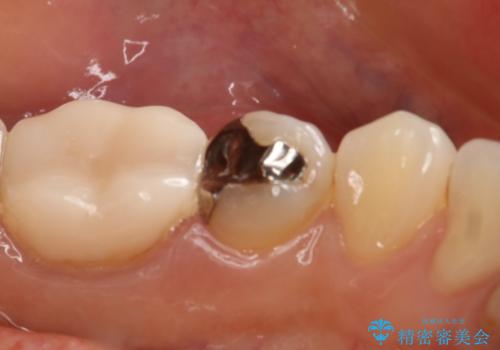

- 左下5番の銀歯をセラミックにやり変え希望の患者様です。

切削量を考慮し、セラミックインレーでの治療を選択しました。

銀歯直下のう蝕を除去しCRで裏層を行った上で、形成・印象を行っています。